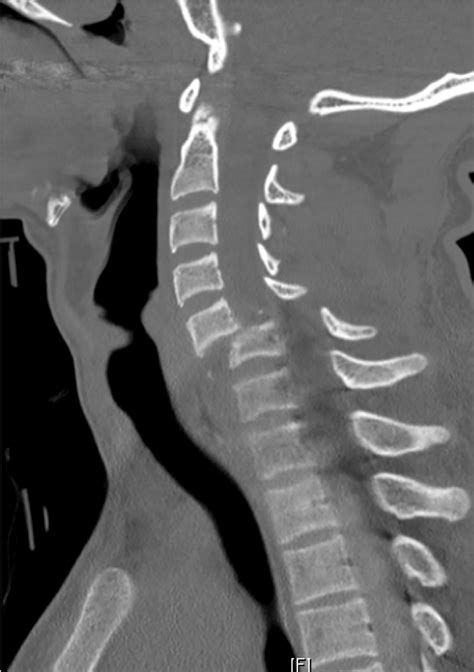

• Multiplanar Reconstruction (MPR): This technique allows for the creation of images in multiple planes (axial, sagittal, and coronal), providing a more comprehensive view of the spine.

Radiologists look for signs of fractures, dislocations, and other abnormalities that could indicate a spinal injury or condition. For example, a fracture may appear as a break in the continuity of the bone, while a dislocation may show misalignment of the vertebrae.

• Fractures: These can range from minor cracks to severe breaks that disrupt the integrity of the bone.

• Dislocations: These occur when the vertebrae are displaced from their normal position, often due to trauma.

• Spinal Stenosis: This condition involves the narrowing of the spinal canal, which can compress the spinal cord and nerves.